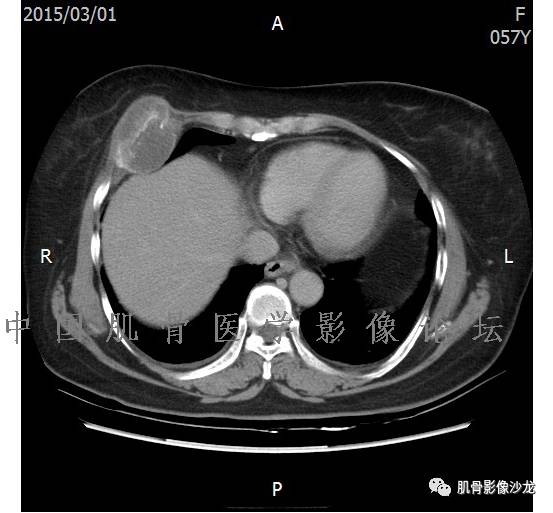

患者2月前无明显诱因下感右腿疼痛、麻木,疼痛呈持续性,发作时无法行走,休息后可缓解。当时无明显肿块,患者遂至当地医院就诊,查X片见右髂骨骨质破坏。6周前患者自觉右髋部渐大肿块,初肿块较小,后肿块逐渐增大,现肿块约12*10cm大小,有压痛。患者遂至我院就诊,查MRI:右髂骨异常信号,伴软组织肿块。ECT、肺CT未见转移。现患者为求进一步治疗,门诊拟“右髂骨肿块 ”收治入院。 患者发病来,神清,精神可,胃纳夜眠可,二便无殊,体重无明显变化。

1、软骨肉瘤可以有膨胀性骨质破坏(病例3,4),可以有溶骨性骨质破坏(病例2),局部皮质因为破坏变薄,中断 ;

2、软骨基质T2WI高信号,软骨小叶分叶状,也就会出现高老师提到的骨内膜扇贝形压迹。一般认为骨内膜扇贝形压迹超过骨皮质厚度的2/3是软骨肉瘤在长管状骨的特征性表现。如上图。3、软组织肿块或肿胀;

4、 钙化,环形,弓形,边缘模糊 ;

5、增强后进行性延迟,不均匀分割状强化, 会强化的纤维间隔,软骨小叶不会强化,关于老师们说到的钙化,软骨肉瘤不一定会有钙化 。